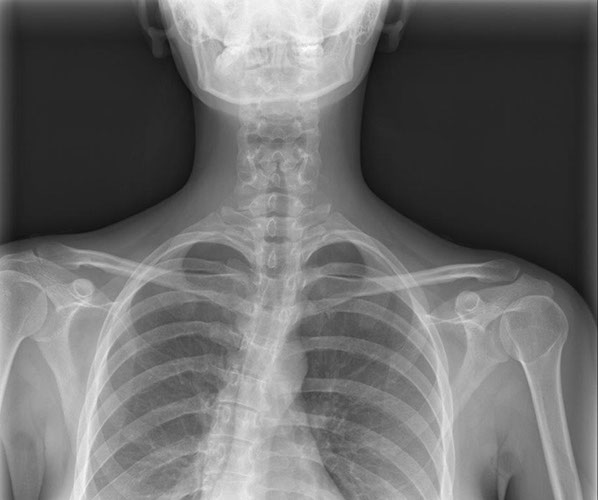

Herz-/Lungenröntgen (Thorax-Röntgen)

Untersuchungsablauf:

Die Untersuchung muss mit tiefer Einatmung (Inspiration) durchgeführt werden. Dies erlaubt eine bessere Beurteilbarkeit der Lunge. Es ist auch wichtig, dass Sie sich während der Aufnahme nicht bewegen. Es werden zwei Aufnahmen im Stehen gemacht. Im Anschluss an das Röntgen wird von der Radiotechnologin die Bildqualität geprüft und erfolgt danach die Befundung durch den Radiologen.